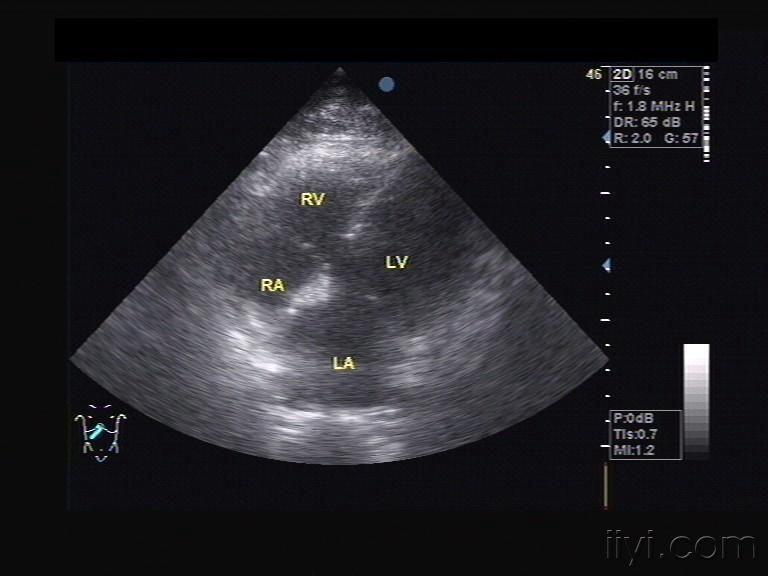

镜面右位心的超声模板

镜面右位心的超声模板,镜面右位心报告书写